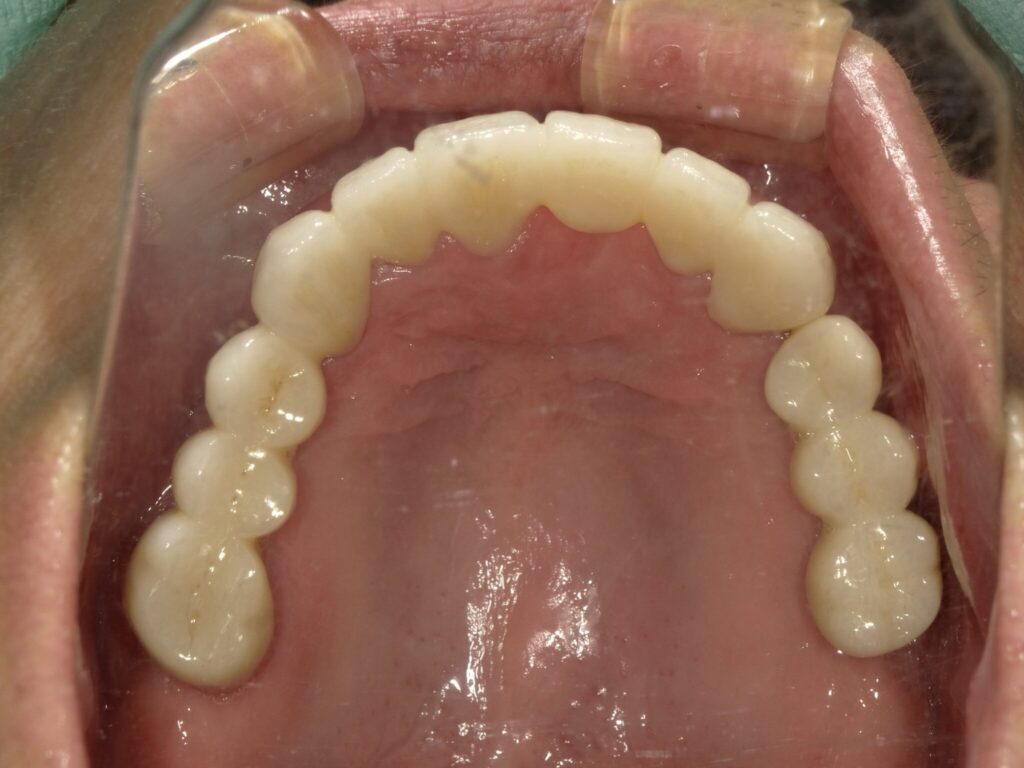

全顎治療症例

| 主訴 | 全体的に見た目を綺麗にしたい。奥歯でしっかり噛みたい。 |

| 診断名・ 主な症状 |

臼歯部欠損 |

| 治療内容 | インプラント埋入(左下5・6,右下5・6,左上4・6) サイナスリフト(左上4・6) ジルコニアBr(右上6−左上3) E –MAX CAD(右下4) セラミックインレー(左下4) |